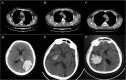

Intracerebral hemorrhage (ICH) is a common and severe neurological disorder and is associated with high rates of mortality and morbidity. ICH is associated with old age and underlying conditions such as hypertension and diabetes mellitus. The COVID-19 pandemic is associated with neurological symptoms and complications including ICH. For instance, the mechanisms by which COVID-19 may contribute to hemorrhagic stroke may include both depletion of angiotensin converting enzyme 2 (ACE2) receptor and overactive immune response. In this study, we herein report three patients (0.25%) out of 1200 admissions with COVID-19 to our center between 1 May and August 4, 2020, who developed ICH. In addition, we will briefly discuss the possible pathophysiological mechanisms of COVID-19 infection in patients with ICH.